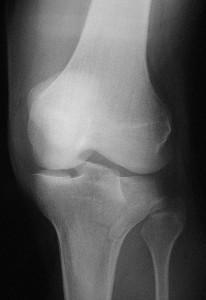

The knee is a complex hinge-type joint that bears tremendous pressure during all weight-bearing activity. Competitive athletes, weekend warriors and casual strollers alike depend upon smooth, pain-free range of motion of the knee joint for optimal function.